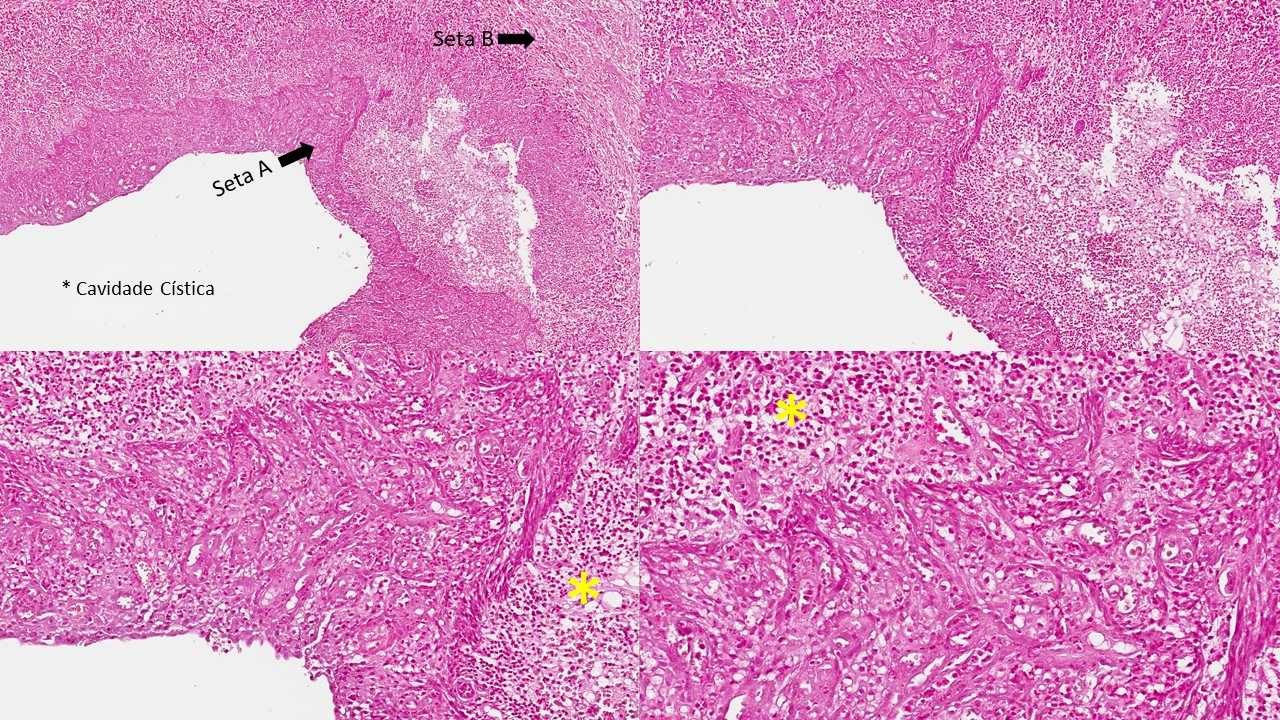

Cisto envolvendo a coroa do dente não irrompido. A cavidade cística está voltada para a coroa (se forma entre a coroa e o tecido pericoronário) e o tecido epitelial que reveste a cavidade apresenta-se estratificado com número variável de camadas de células e não ceratinizado. Em algumas áreas o epitélio encontra-se hiperplasiado (Seta A). Entretanto, originalmente apresenta 2-4 camadas de células. As células epiteliais podem ser células cúbicas, mucosas ou ciliadas. A cápsula de tecido conjuntivo fibroso denso (Seta B) neste caso exibe intenso infiltrado inflamatório linfoplasmocitário (asterisco amarelo) e hemorragia. Pode haver presença de remanescentes odontogenicos.

Dados importantes para o diagnóstico:

- Cavidade cística envolvendo a coroa do dente totalmente incluso;

- Epitélio estratificado pavimentoso não ceratinizado (quantidade variável de camadas);

- Cápsula de tecido conjuntivo fibroso denso;

Cisto inflamatório que ocorre na margem cervical, lateralmente à raiz, relacionado com dentes em erupção ou parcialmente erupcionados com acúmulo de biofilme como agente causador da inflamação e estimulo à formação do cisto.

Descrição microscópica:

Cavidade cística contornada por tecido epitelial estratificado pavimentoso não ceratinizado hiperplásico (Seta A). A cápsula de tecido conjuntivo subjacente exibe vasos sanguíneos, hemorragia, infiltrado inflamatório crônico difuso (Seta B).

Dados importantes para diagnóstico:

- Envolvendo a coroa de um dente parcialmente erupcionado;

- Cavidade cística;

- Epitélio estratificado pavimentoso não ceratinizado hiperplásico;

- Tecido conjuntivo fibroso denso contendo vasos sanguíneos, células inflamatórias crônicas (asterisco amarelo) e fibras colágenas que compõem a cápsula fibrosa.